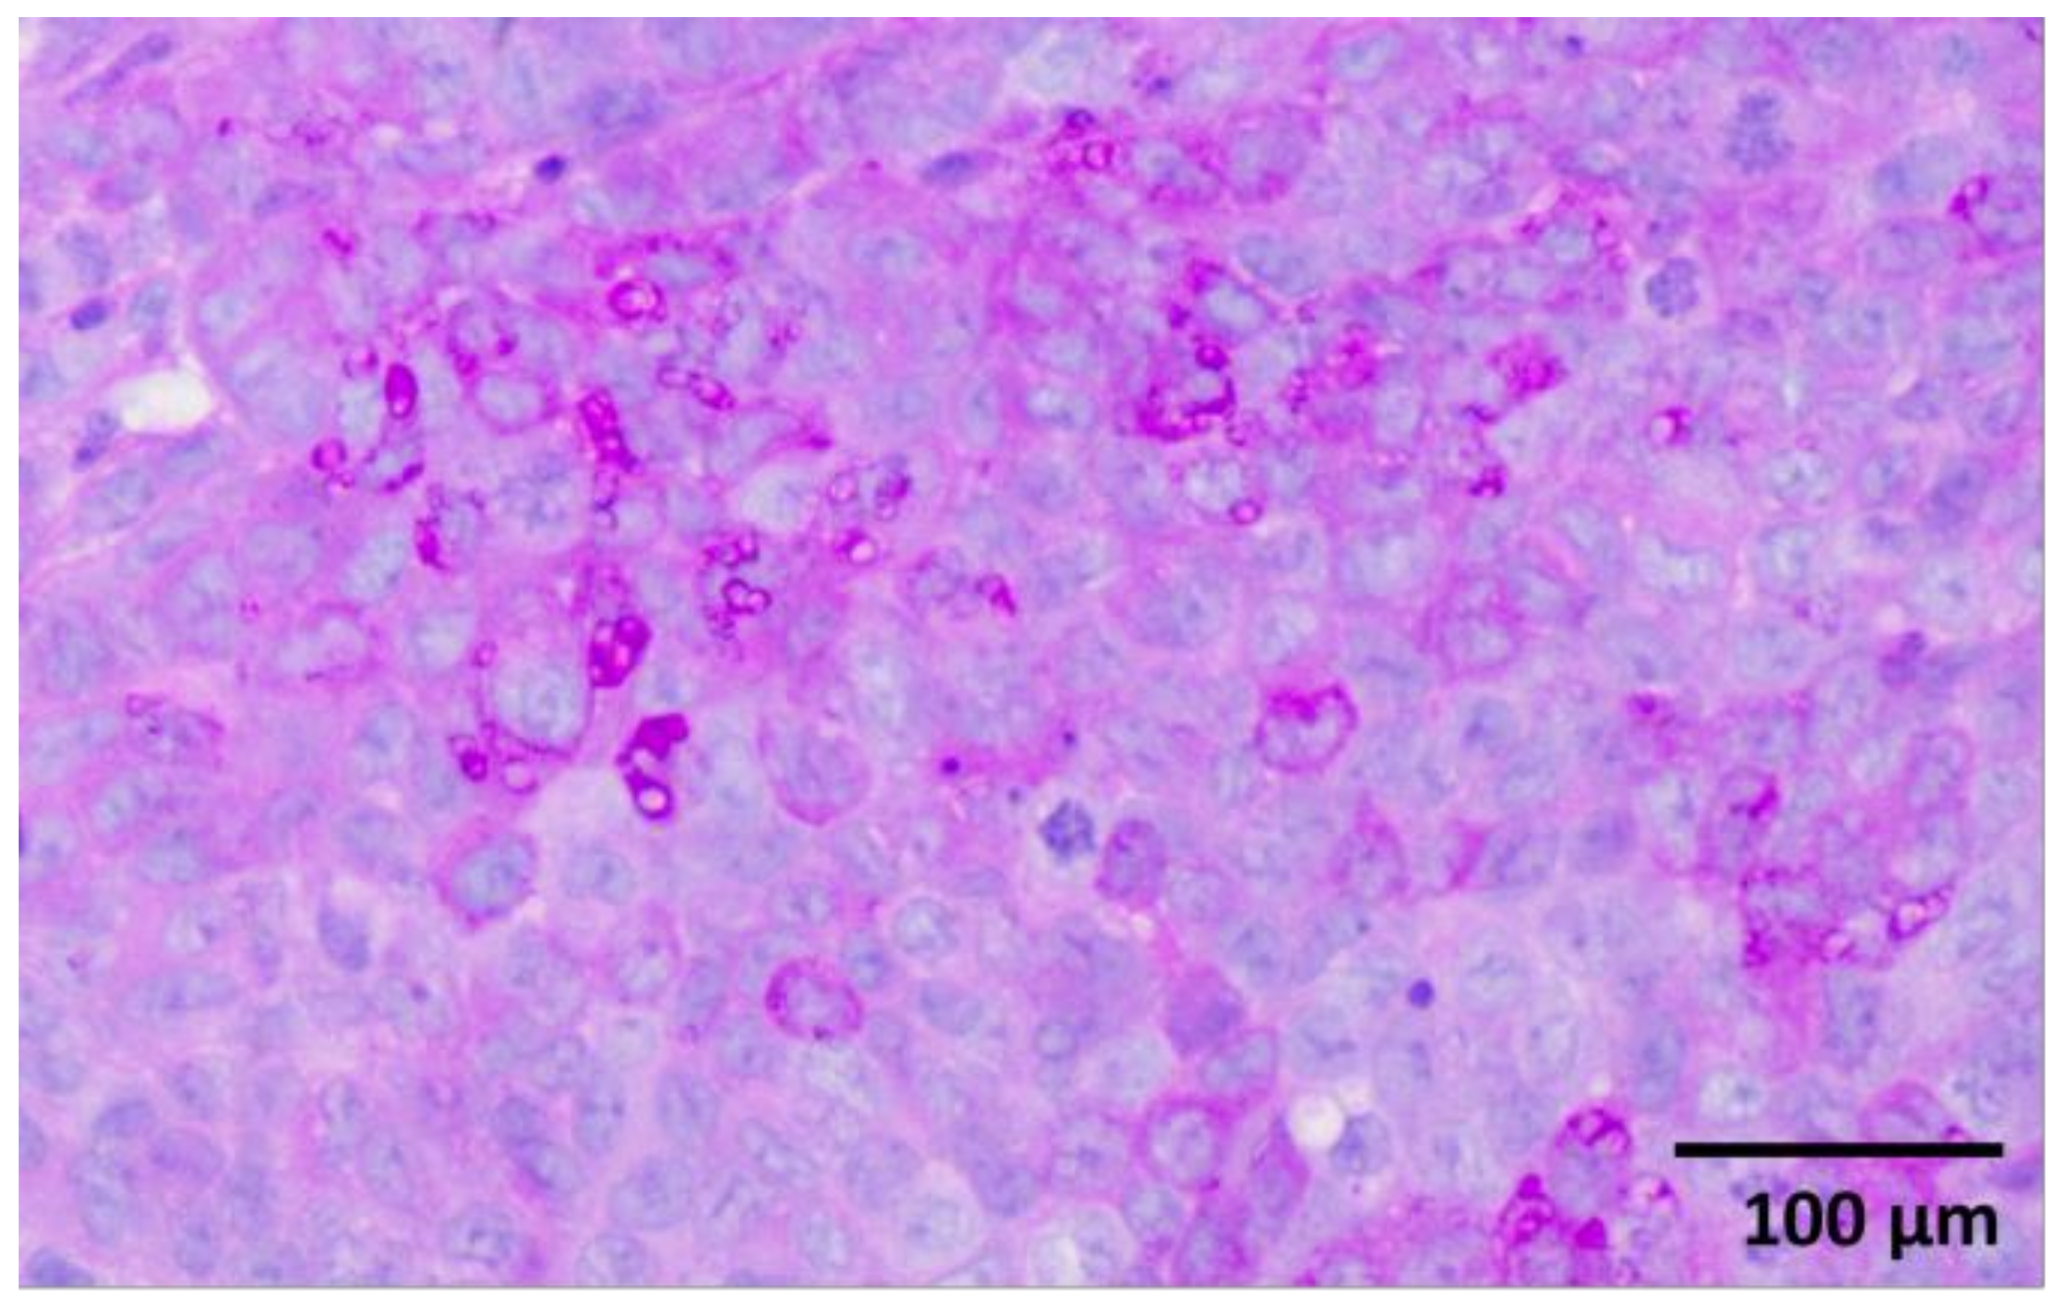

2.1. Histological Evaluation

Histological examination revealed a palpable subcutaneous tumor that was a moderate to low differentiated colon carcinoma, depicted in Figure 1a,b; it thus provided indispensable evidence for their classification in the experimental spectroscopic analysis. Each tumor mass was surrounded by fibrous stroma, as indicated by the black arrow in Figure 1a. The tumor cells were enlarged with round or oval nuclei, and the mitotic activity was increased, as illustrated in Figure 2. The central regions of the tumors were necrotic with hemorrhage, tumor-infiltrating cells, and macrophages, as can be observed in Figure 3a,b. Finally, the Foci of PAS-positive mucin-producing tumor cells are also observed and illustrated in Figure 4.

Figure 2. Increased atypical mitotic figures (arrows). H&E staining X400.